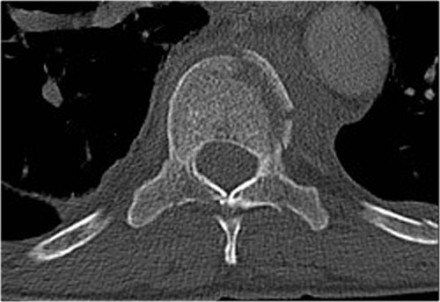

Widening of the interpedicular distance

Widening of the interpedicular distance, often a result of the sagittal fracture, is seen in 80% of burst fractures.

The lateral view shows the typical features of a burst fracture.

On the AP-view notice the subtle widening of the interpedicular distance compared to the levels above and below.

The axial CT and MRI in the same patient show the displaced fragment pressing on the thecal sac.

On the sagittal CT and MRI there are no signs of posterior ligamentous injury.

The anterior longitudinal ligament is disrupted.

The right facet joint looks a bit widened on the CT and there is some fluid in the joint on the MRI.

If there was a lot of fluid in the joint, we should call this indeterminate.

In this case we are not sure.